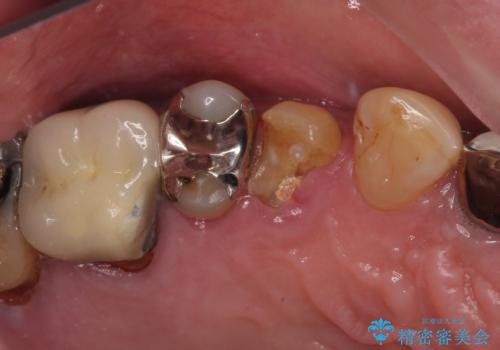

奥歯が取れた フルジルコニアクラウン

担当医 小澤俊哉